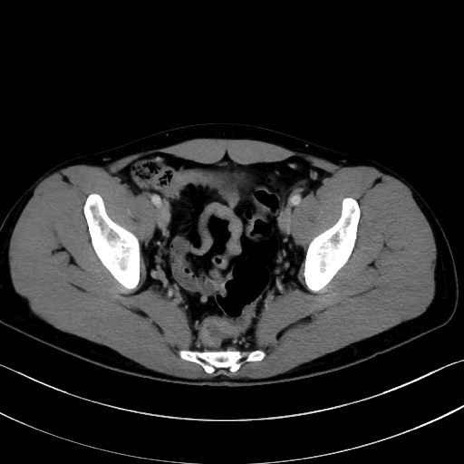

6. 大腿内側(内転筋群)

恥骨筋 (Pectineus)

長内転筋 (Adductor longus)

短内転筋 (Adductor brevis)

大内転筋・小内転筋 (Adductor magnus / Adductor minimus)